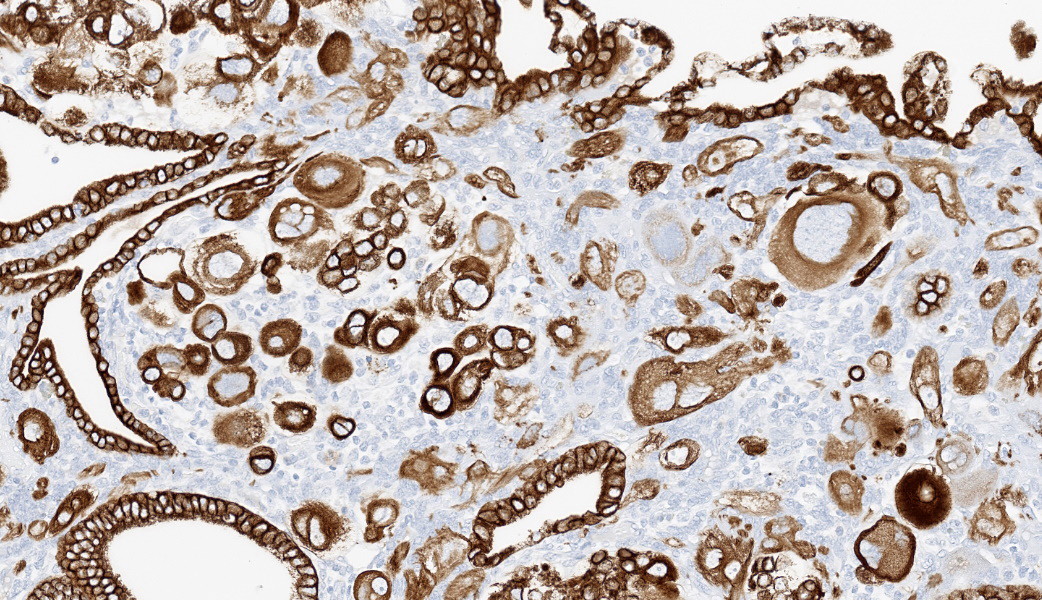

Immunohistochemistry on the uterine neoplasm is performed using anti-human chorionic gonadotropin (hCG), anti-pancytokeratin AE1/AE3, anti-human placental lactogen (huPL), anti-p63, anti-CD10, anti-placental alkaline phosphatase (PLAPH), anti-progesterone receptor (PR), anti-estrogen receptor α (ERα), and anti-Ki67 antibodies and is visualized using 3,3′-diaminobenzidine or Fast Red as a chromogen. Occasional neoplastic cells with high degrees of atypia express cytoplasmic labeling for hCG. Neoplastic cells have strong cytoplasmic and membranous labeling for pancytokeratin AE1/AE3. Labeling for huPL and CD10 demonstrates rare neoplastic cells expressing moderate to strong cytoplasmic immunolabeling; however, the majority of neoplastic cells are negative. Few neoplastic cells have weak nuclear p63 labeling. Labeling for Ki67 demonstrates moderate to high numbers of proliferative neoplastic cells regionally. Overall, PR and ERα expression is limited due to the immature age of the animal, but is present in the expected locations in the endometrial stroma and glandular epithelium, and absent in the neoplastic population. Neoplastic cells do not label for PLAPH. These immunohistochemical findings further support a diagnosis of choriocarcinoma.

Choriocarcinoma is a neoplasm of trophoblastic lineage that most often arises in women following normal or abnormal pregnancies.1 Diagnostic features include highly pleomorphic, polygonal to round cells with abundant cytoplasm that are both uninucleate (cytotrophoblast or intermediate trophoblast-like) and multinucleate (syncytiotrophoblast) cells, and often a high mitotic rate with metastasis. Morphologic features on histologic evaluation of hematoxylin and eosin-stained uterus from this sexually immature cynomolgus macaque were consistent with choriocarcinoma.In human medicine, choriocarcinoma falls under the umbrella entity of gestational trophoblastic disease. Other neoplasms in this entity include placental site trophoblastic tumor (PSTT) and epithelioid trophoblastic tumor (ETT). PSTTs are composed of a monomorphic population of large, pleomorphic cells derived from implantation-type intermediate trophoblasts. Most cells are uninucleate, but it is not uncommon to see occasional scattered multinucleate cells. ETTs arise from chorionic-type intermediate trophoblasts and present as nests, cords, or solid masses with a monomorphic population of small, round cells.1 Choriocarcinomas tend to have a distinct morphology compared to PSTT and ETT with the presence of uninucleate and multinucleate cells; however, a panel of immunohistochemical markers is commonly used to confirm diagnosis. Characterization with antibodies against hCG, pancytokeratin AE1/AE3, huPL, p63, CD10, PLAPH, and Ki67 provides further support for a diagnosis of choriocarcinoma. These immunohistochemical markers are helpful in distinguishing between PSTT, ETT, and choriocarcinoma (see table).5

The contributor of this case provides a great overview of choriocarcinomas, their main differentials, and the common immunohistochemical profiles expected with these neoplasms in their comment. These topics covered much of what was discussed in conference for this case.The topic of the IHCs prompted a review of what each of the pertinent markers is for and what some of the IHC targets do physiologically. For example, choriocarcinomas are readily immunoreactive for human chorionic gonadotropin (hCG). In the body, hCG (or any of the species-specific CGs, for that matter), is produced by the placental trophoblasts (the cell of origin in choriocarcinoma) and stimulates the release of progesterone from the corpus luteum (CL) to maintain the pregnancy. Human placental lactogen (HPL) also functions as a marker for trophoblasts and is released by the placenta to, among other functions, stimulate growth of the mammary glands for lactation. CD10 marks endometrial stroma. Inhibin, released from granulosa cells (GC) to regulate production of follicle-stimulating hormone (FSH), will be immunoreactive in granulosa cells (including in some neoplastic GC populations). Although choriocarcinoma is classified as a germ cell tumor, it is weakly to not at all immunoreactive for placental-like alkaline phosphatase (PLAP), which is a marker of germ cells. This is thought to be due to the neoplastic choriocarcinoma cells being less well-differentiated or potentially even de-differentiated compared to regular syncytiotrophoblasts, which are usually immunoreactive for PLAP.6 Lastly, p63, a member of the p53 “Guardian of the Genome” family of genes, will be immunoreactive in myoepithelial cells, squamous epithelial cells, and a few others. The table provided by the contributor provides an excellent resource for cross-comparison of IHC profiles between these in choriocarcinomas and their differentials.5